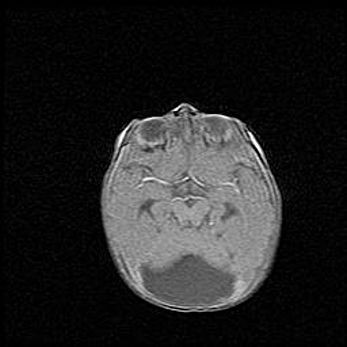

Церебральная ишемия II.

Возраст: 7 дней

Вес: 3350 г

Пол: женский

Окружность головы: 35 см

Срок гестации: 39 недель

Ишемия головного мозга – это состояние, которое развивается в ответ на кислородное голодание вследствие недостаточного мозгового кровообращения. У новорожденных она является следствием дефицита кислорода, что ведет к метаболическим расстройствам различной степени тяжести в тканях головного мозга, в том числе к развитию коагуляционных некрозов и гибели нейронов.